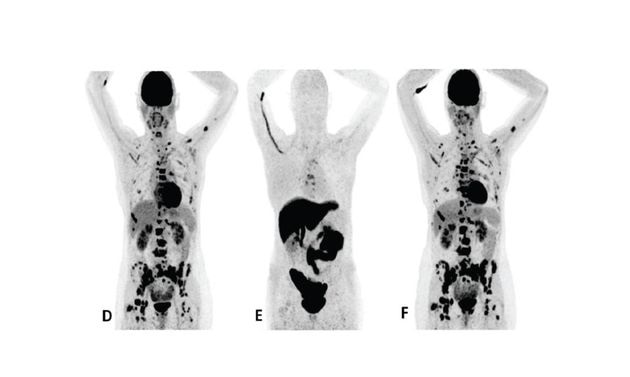

F18 fluoroestradiol and FDG PET images in a MBC treatment responder and non-responder*†15

Patient 2 (anterior/superior) did not respond to treatment with an AI and a CDK 4/6 inhibitor*15

Upper row responder: Baseline FDG PET (A) showed pathological uptake in axillary lymph nodes (right side) and in nearly all vertebrae and pelvic bones. Image B showed the baseline F18 fluoroestradiol PET with pathological ER expression in the axial skeleton (including vertebrae, pelvic bones, proximal humeri and femora) and in axillary lymph nodes (right side). After 8 weeks, the FDG PET (C) showed almost complete metabolic response (just some slightly elevated uptake in the axillary lymph nodes). The patient had been on treatment for more than 70 weeks. Lower row non-responder: Baseline FDG PET (D) showed pathological uptake in multiple skeletal lesions. Image E showed the baseline F18 fluoroestradiol PET with only some increased ER expression in thoracic vertebrae. After 8 weeks, the FDG PET (F) showed no metabolic response, even some increase in the pathologic uptake in the multiple skeletal lesions.15

Images from a prospective, single center, feasibility study that aimed to explore whether baseline F18 fluoroestradiol PET discordance and F18 fluoroestradiol uptake were correlated with outcome and response to concomitant treatment with an AI and a CDK 4/6 inhibitor. Thirty patients with ER+ MBC were included in the study, including 87% who received at least one previous line of ET in the metastatic setting.15